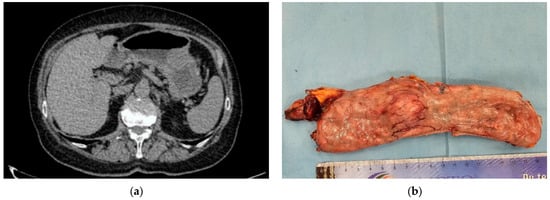

- Moga, D.; Popentiu, A.; Popa, D. Laparoscopic Wedge Resection for Gastric Mesenchymal Tumor–Small Case Series. Rom. J. Mil. Med. 2023, 126, 239–244. [Google Scholar] [CrossRef]

- Costache, M.F.; Filip, B.; Scripcariu, D.V.; Danilă, N.; Scripcariu, V. Management of Gastric Stromal Tumour-Multicenter Observational Study. Chirurgia 2018, 113, 780–788. [Google Scholar] [CrossRef] [PubMed]